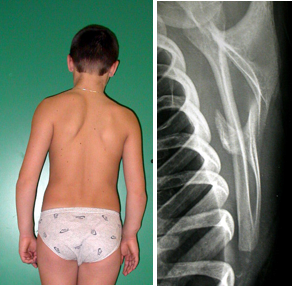

Una scoliosi vera (fig. 2) , può dare un’alatura monolaterale della scapola dal lato della gibbosità toracica.